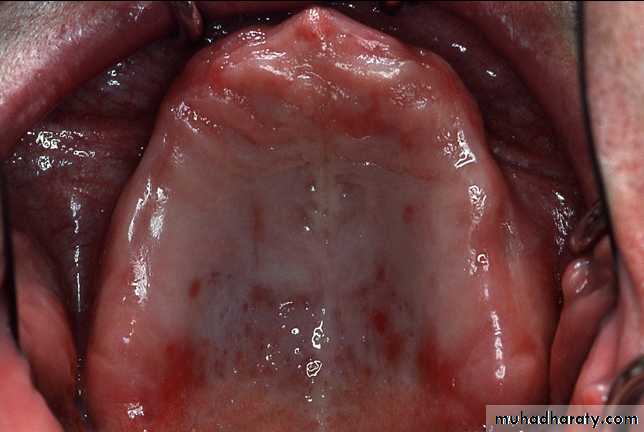

MAXILLARY IMPRESSION

incisive papilla

b. palatal rugaec. median palatine raphe

d. maxillary tuberosity

e. pterygomaxillary notch

f. fovea palatini and vibrating line area

i. residual alveolar ridge

j. buccal frenum

k. labial frenum